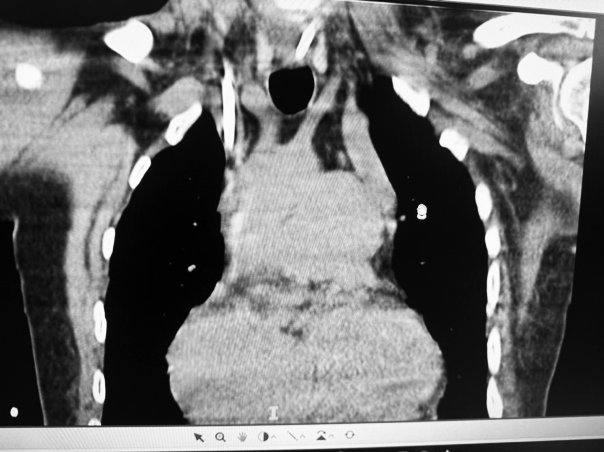

Presentamos un paciente con hiperamoniemia, que durante el estudio de la causa se diagnosticó agenesia de la vena porta, con anastomosis de la vena mesentérica a la vena renal izquierda. Ante el cuadro clínico y humoral, con compromiso neurológico, se decidió la colocación de un catéter doble lumen y se inició tratamiento mediante hemodiálisis convencional. Se colocó catéter por vía yugular izquierda presentando ubicación atípica y con mala cinética por lo que debió colocarse otro catéter doble lumen en vena subclavia derecha, ubicándose en posición convencional. La radiografía de control muestra la ubicación de ambos catéteres colocados.

Además de la anomalía vascular de la vena porta y de las cavidades cardíacas que presentes en este paciente, se detectó una anomalía vascular en las venas centrales. Se debe tener presente la posibilidad de que exista esta asociación de variantes anatómicas cuando debemos abordar vías centrales, en nuestro caso con catéter de doble lumen para tratamiento dialítico. El tip del catéter izquierdo se ubicó a nivel de seno coronario, donde el flujo sanguíneo resultó deficiente para efectuar el tratamiento dialítico. Se adjunta gráfico con esquema de las alteraciones más frecuentes de la vena cava superior doble.(1)

La TAC mostró una vena cava superior izquierda y otra derecha